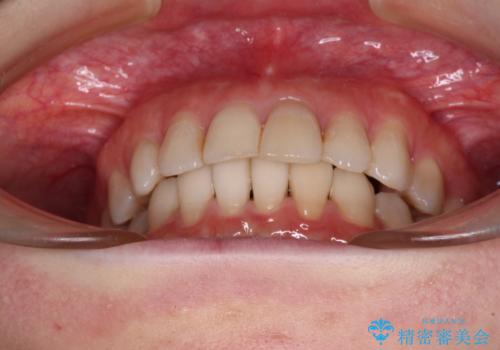

前歯の突出感とデコボコをインビザライン矯正で改善

- 上下前歯の突出感とデコボコを気にして来院された患者様です。

インビザラインによる上下歯列の側方拡大と後方移動、IPR(歯と歯の間を削る)にるスペースの獲得により歯列を整えることとしました。

骨格的な左右差があったため、上下の正中を合わせることができませんでした。

骨格の差は改善できないため、奥歯の咬み合わせに物足りなさを感じましたが、奥歯の咬み合わせによる不自由はなく、口元の突出感も改善することができました。